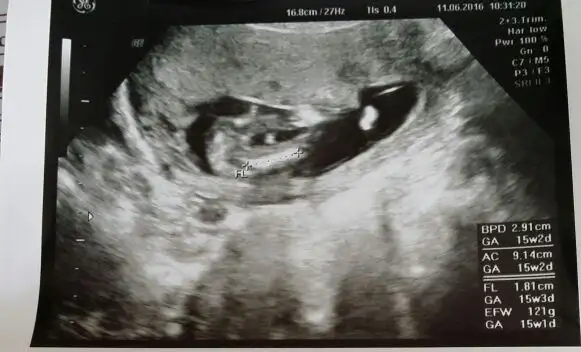

Arkadaşlar ne güzel herkes cinsiyetleri öğreniyor , bana doktorum 16_18 hafta arası gel Aft testi yapalım demişti hesapladım bayramdan önce gitmem gerekiyor hem cinsiyette kesinleşir merakım gider bari :) 30 haziran a randevu alcam kısmetse bakalım..